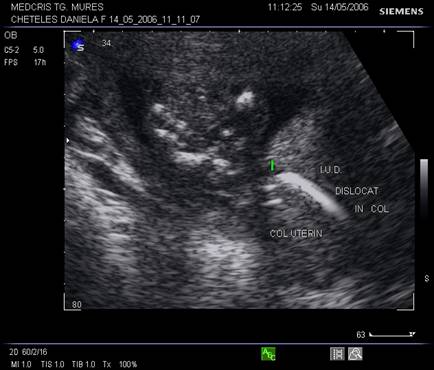

8.Sarcina si dispozitivul intrauterin

Pacienta purtatoare de IUD va fi examinata pentru a stabili locul dispozitivului in cavitatea uterina. Daca acesta a fost evacuat sarcina va continua fara risc. Daca IUD este inca intracavitar, va trebui decis daca trebuie extras in functie de pozitie si de varsta sarcinii.

Ecografic, dispozitivul apare ca o structura ecogena cu forma variabila, localizat alaturi deasupra sau sub sacul gestational, eventual in canalul cervical.

Daca dispozitivul intrauterin prin pozitia sa nu poate fi extras, continuarea sarcinii poate fi grevata de cresterea riscului de avort, infectii, perforatii, nasteri premature. Prezenta asocierii IUD cu sarcina nu constituie indicatie de avort si nu creste riscul de anomalii fetale.

La pacientele cu teste pozitive si IUD prezent se va cerceta cu grija regiunea anexiala bilateral pentru a exclude o sarcina ectopica.

Fig nr. 90. Dispozitiv intrauterin dislocat in col, la o sarcina de 17 saptamani